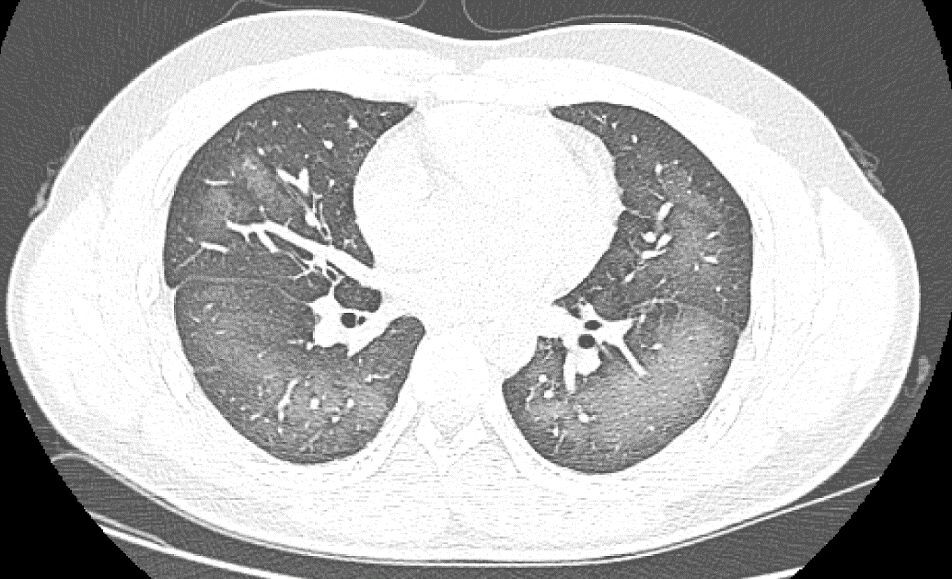

日前,20岁的长沙小伙李林(化名)在外出前使用了防晒喷雾,在对着面部喷洒时一不小心误吸,随即出现胸闷、咳嗽的症状。症状一直持续到第二天仍未好转,他急忙来到湖南省长沙市第三医院就诊。

经检查,肺部CT片显示,李林双肺赫然呈现大范围白色样病变,报告提示“白肺”。

“白肺”一般是指重症肺炎在X线或CT检查下的表现,患者肺部呈现一大片的白色状态,往往会出现呼吸困难、呼吸衰竭,严重者还会出现其他脏器功能障碍。

长沙市第三医院放射影像科的接诊医师表示,除了感染、弥漫性肺泡出血综合征等“白肺”最常见的病因外,吸入有害物质如粉尘、喷雾等,也可导致肺部出现大范围白色样病变。这位年轻的患者就是因为使用不当,吸入了一部分防晒产品进入肺部,导致“白肺”的发生。